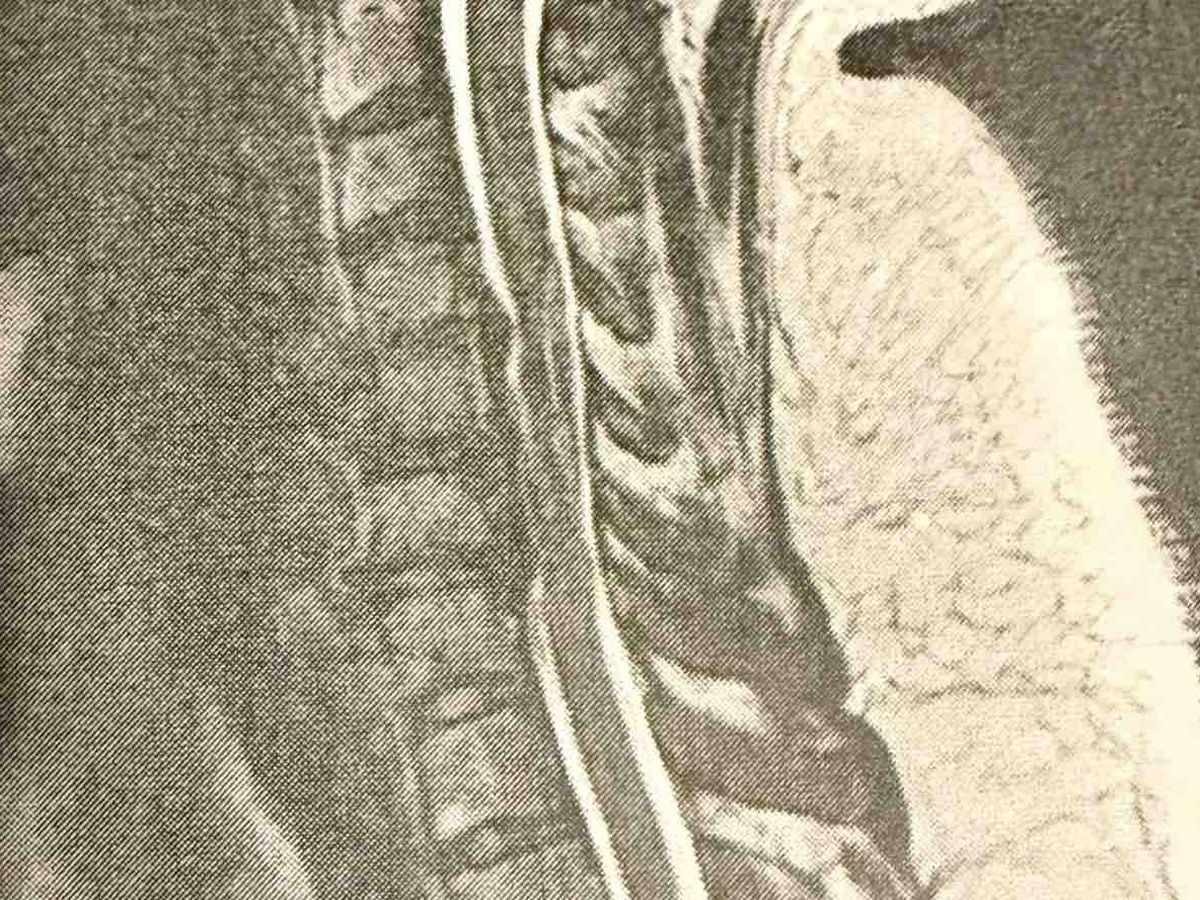

I’m disabled and homebound from a spinal cord injury and live with chronic pain and degenerative diseases.

Every day is a struggle, and I can’t perform daily activities of living. I have permanent nerve damage and lose feeling in my legs, feet and right hand. My right hand is partially paralyzed. I’m no longer able to drive or write, and have limited mobility.